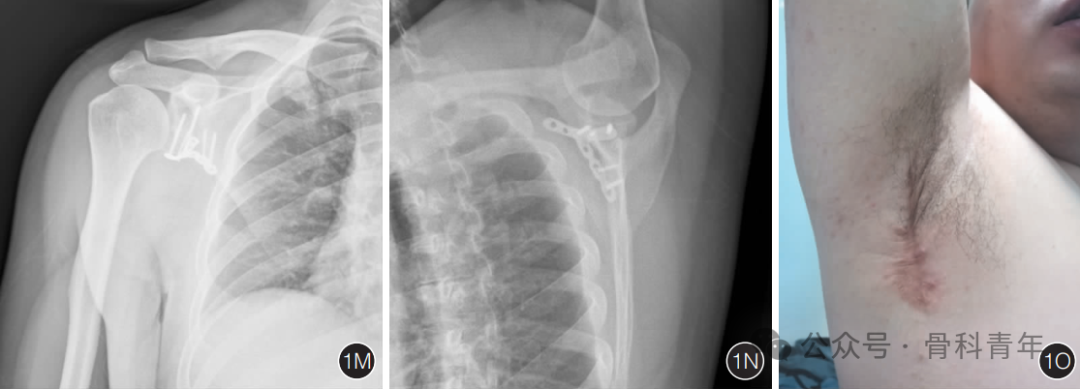

三、临床疗效

研究团队文献发表中已总结了40余例的病例资料,已证实在对肩胛盂前下方骨折的内固定中,腋窝入路可获得良好的治疗效果。